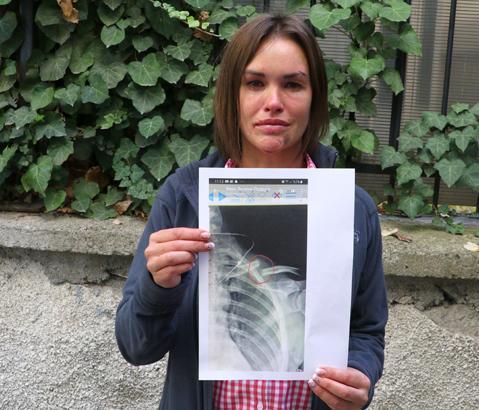

Ankara’da güzellik uzmanı Rus Vera Chikareva (35) kendisine şiddet uyguladığı için evi terk edip, boşanmaya karar verdiği eşi Salih G. (41) tarafından uzaklaştırma tedbirine rağmen öldüresiye dövüldü. Köprücük kemiği kırılan ve hastanede 1 haftaya yakın tedavi gören Chikareva, daha önce de 3 kez kendisini dövdüğünü ileri sürdüğü eşinin cezalandırılmasını istedi.

Köprücük kemiği kırılan ve hastanede 1 haftaya yakın tedavi gören Chikareva, daha önce de 3 kez kendisini dövdüğünü ileri sürdüğü eşinin cezalandırılmasını istedi.

Tedavi altına alınan Chikareva'nın köprücük kemiğinin kırıldığı belirlendi. Tedavisi tamamlanan Chikareva, darp raporu alarak eşinden şikayetçi oldu. Gözaltına alınan Salih G., çıkarıldığı mahkemece serbest bırakıldı.

O sonra kaçtı ama ben ayakta duramadım. Köprücük köpüğüm kırılmıştı. 4 gün yattım, bir şey yiyemedim.